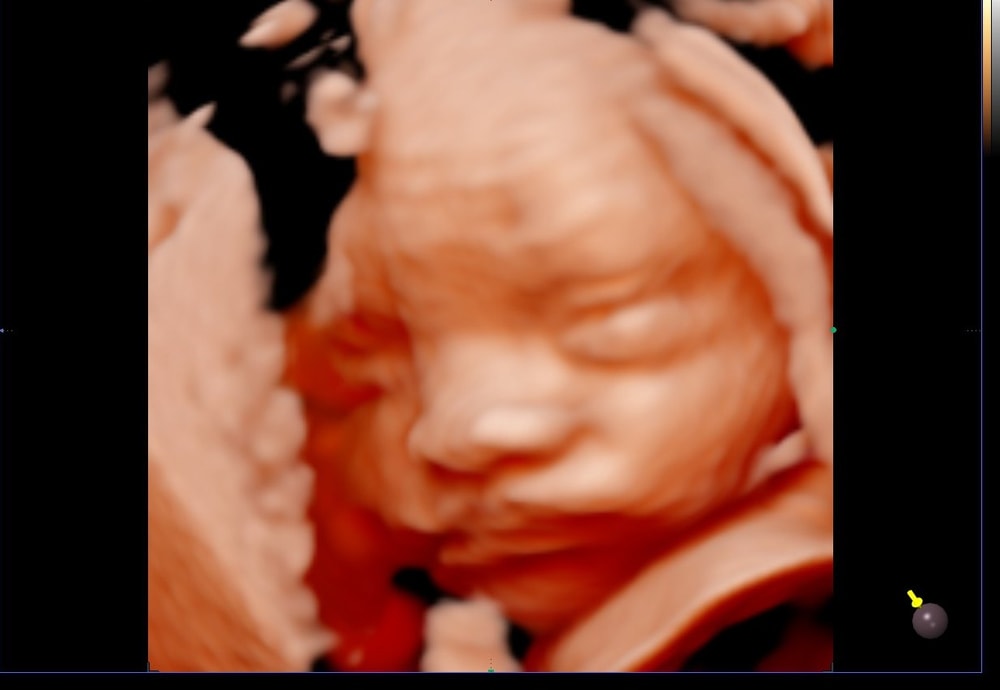

31 неделя, 3 скрининг

Прошли с малышом 3 скрининг в 31 полную неделю. Улёгся уже головой вниз, Вес 1700, к родам обещают 3300-3400 и 52см, как и первый сын. Высокий тоже)

2 скрининг прошла ещё в январе, теперь жду 3 скрининг в начале апреля, и 15 марта пойду на 5д УЗИ посмотреть на того кто же там живёт.